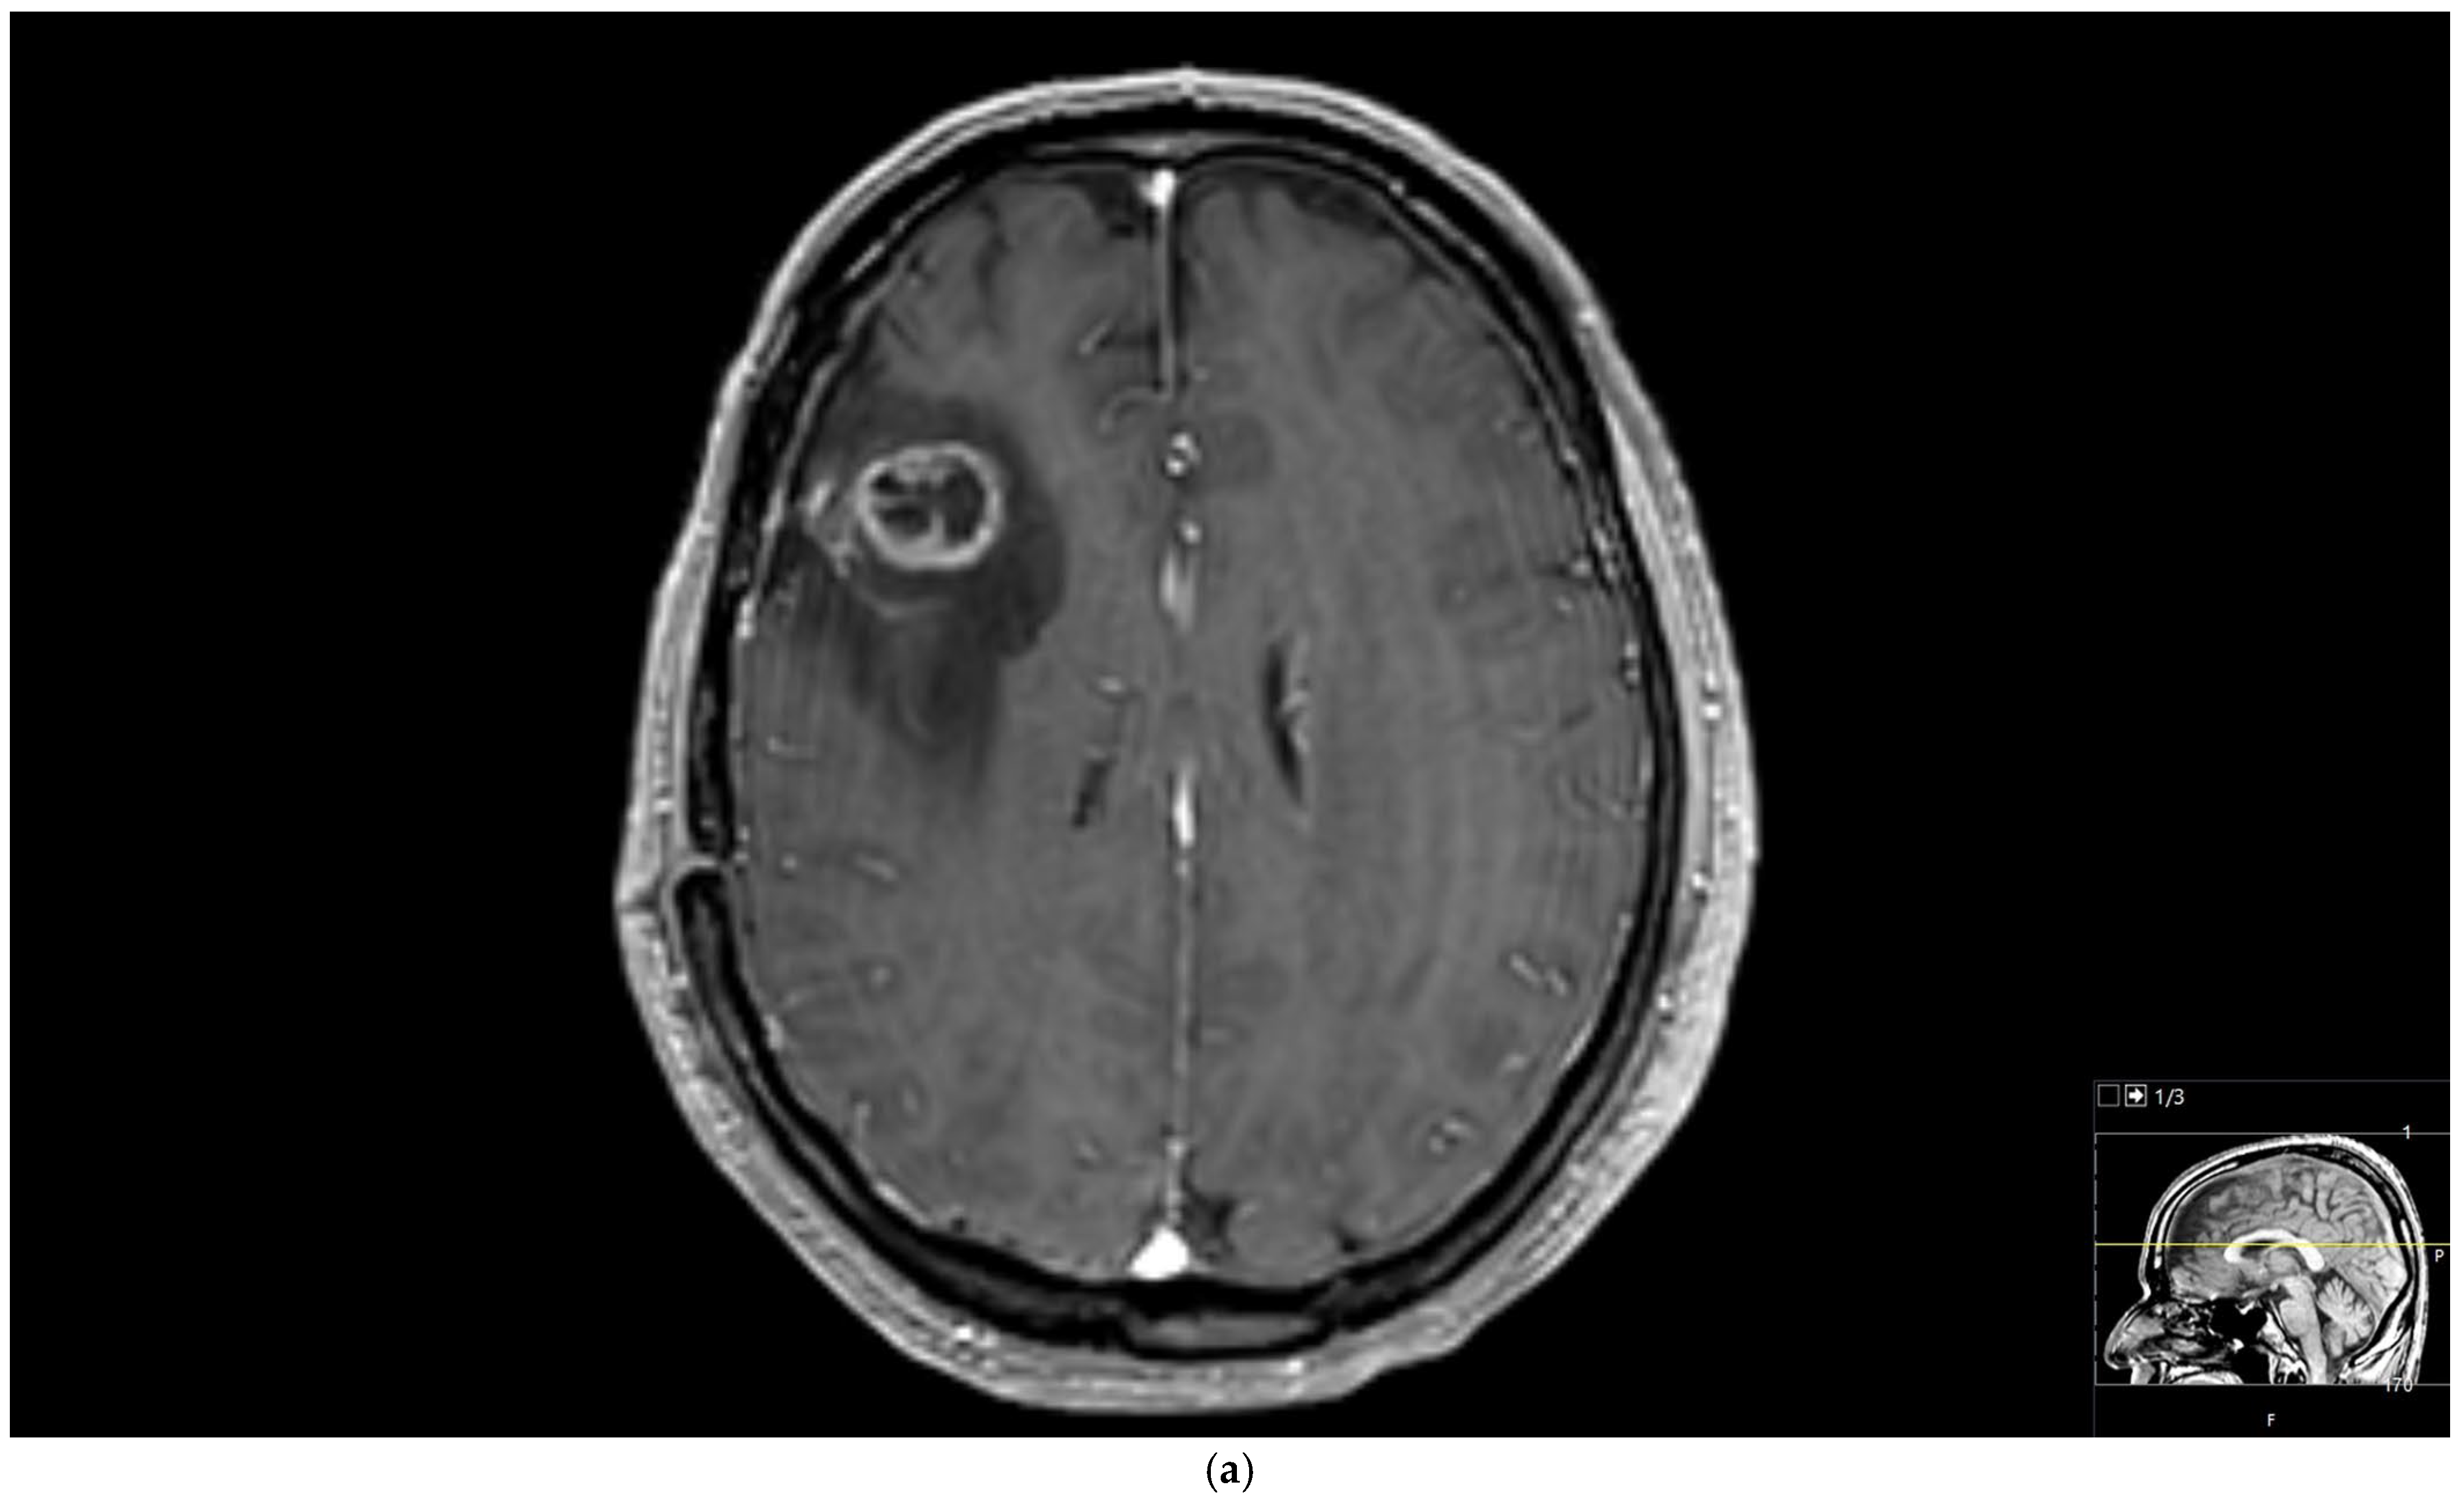

Figure 2. Brain magnetic resonance imaging (MRI) of a 67-year-old male with small-cell lung carcinoma revealed (a) peripherally enhanced right periventricular mass on post-contrast axial T1-weighted image and (b) hyperperfusion with a rCBV of 2.4 in perfusion-weighted imaging. Pink ROI is from metastatic nodule and white ROI is from contralateral parenchyma.